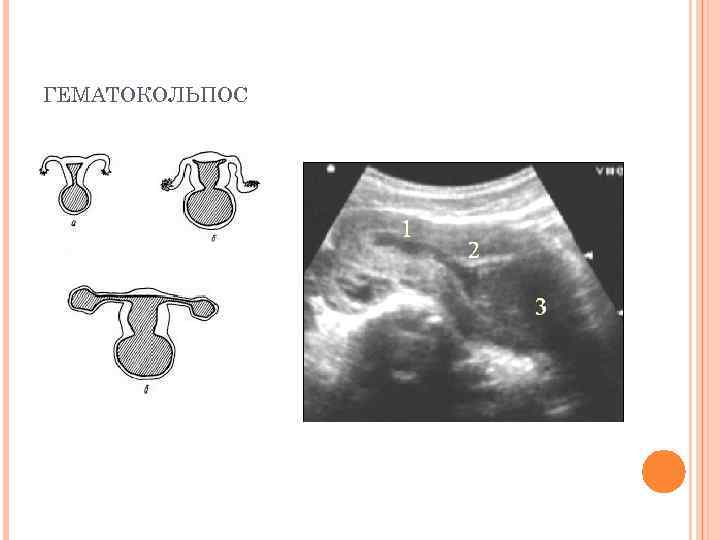

ХАРАКТЕРИСТИКА ЗАБОЛЕВАНИЯ Проявлениями атрезии влагалища могут считаться Ø накопление менструальной крови в вагинальном своде (гематокольпос), накопление крови в полости матки (гематометра), накопление крови в фаллопиевой трубе (гематосальпинкс), накопление слизи в вагине (мукокольпос) а также невозможность или ограничения полового сношения. Ø Ø

ГЕМАТОКОЛЬПОС

СИМПТОМЫ У девочек при наличии первичной формы атрезии с наступлением первой фазы менструаций наблюдаются резкие схваткообразные боли внизу живота, но менструальное кровотечение отсутствует. При гематокольпосе наблюдаются боли ноющего характера, при гематометре — спастические, которые сопровождаются потерей сознания. Атрезия влагалища может быть выявлена и у младенцев. Когда материнский эстроген стимулирует цервикальные и влагалищные железы, он вызывает мукокольпос, при котором заполняется и перерастягивается влагалище слизистым секретом. Выявляется мукокольпос при жалобах ребенка на болезненное мочеиспускание и выявлении в брюшной полости объемных образований. При атрезии сильное растяжение влагалища приведет к гидронефротическому перестроению верхних путей мочевого отдела.

ДИАГНОСТИКА АТРЕЗИИ ВЛАГАЛИЩА Гинекологический осмотр – позволяет разглядеть в половом отверстии куполообразно выделяющийся гематокольпос; Ректо-абдоминальное исследование – показывает высокое расположение увеличенной матки, и при атрезии вагины позволяет обнаружить высоко размещенную, увеличенную матку и трубы. Органы отечны и резко болезненны; Зондирование - определяет глубину вагинального свода и степень патологии. Обычно этот метод используют непосредственно перед хирургической коррекцией влагалища; Бактериологическое и микроскопическое исследование мазка – показывает наличие патогенной флоры в половых органах; Ультразвуковая диагностика (УЗИ) - выявляет наличие, расположение и размеры патологических образований. Особенно хорошо показывает гематометру (пиометру) и гематосальпинкс (пиосальпинкс); Томография органов малого таза (МРТ) – позволяет определить гематокольпос маленького размера; Диагностическая лапароскопия - также успешно применяется для диагностики атрезии; Вагинография - введение контрастного вещества с последующим рентгенографическим исследованием выше зоны поражения. Также дает хорошие результаты. Урологическое обследование – показано при затрудненном оттоке мочи при наличии свищевого пиокольпоса.